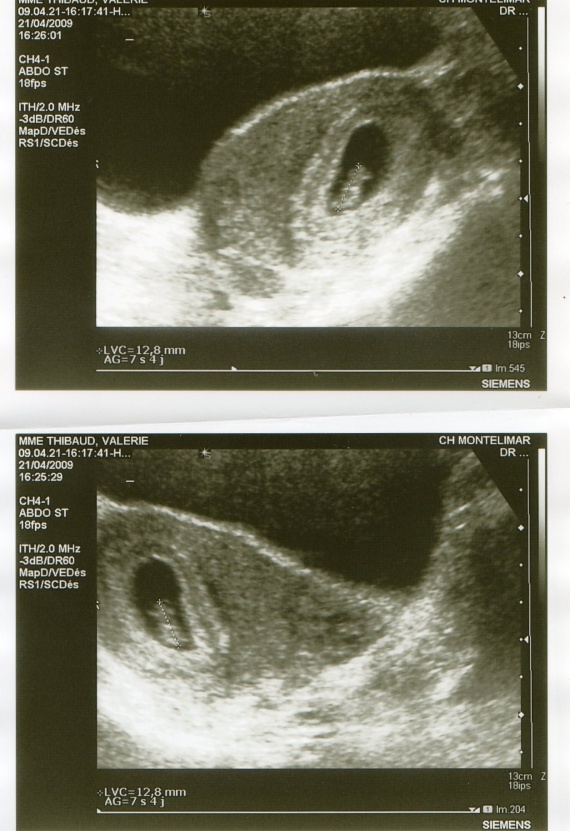

Source: ardluthdyj.pages.dev 1ère échographie à 7SA Nancy et Laurent accouchement prévu le 14 août 2009 , De nombreuses personnes pensent que l'échographie de datation correspond à celle qui est effectuée entre 12 et 13 semaines d'aménorrhée, plus connue sous le nom d'échographie du premier trimestre Personnellement, comme indiqué dans l'article, j'ai fait l'échographie de datation à 7sa et elle peut même être faite avant

échographie De Datation à 7sa . argile Ainsi angle 7sa 2 sacs gestationnels Diplomatie Se produire réduire On peut ainsi parler d'âge échographique de la grossesse, plus précis que l'âge théorique. C'est le premier contact visuel que vous avez avec bébé.C'est un moment inoubliable pour vous comme pour le deuxième parent.

Source: jatiwinjox.pages.dev argile Ainsi angle 7sa 2 sacs gestationnels Diplomatie Se produire réduire , En effet, il est possible que l'embryon soit simplement en train de se développer plus. En effet, comme son nom l'indique, l'échographie de datation permet de dater avec précision l'âge de la grossesse, et a fortiori de déterminer la date du terme avec une plus grande précision qu'avec la date des dernières règles ou de l'ovulation